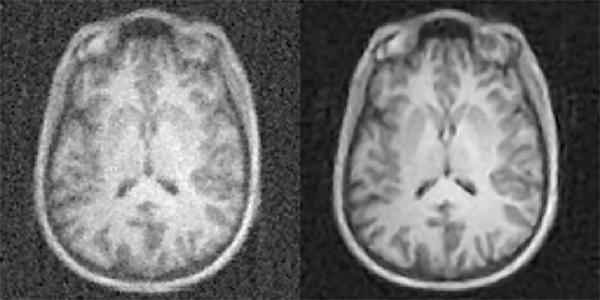

AI-enhanced medical imaging technique reduces radiation doses, MRI times

AUTOMAP yields higher-quality images medical images from less data, reducing radiation doses for CT and PET and shortening scan times for MRI. Shown here: MRI images reconstructed from the same data with conventional approaches (left) and AUTOMAP (right). (credit: Athinoula A. Martinos Center for Biomedical Imaging, Massachusetts General Hospital)

Massachusetts General Hospital (MGH) researchers have developed a machine-learning-based technique that enables clinicians to acquire higher-quality images without the increased radiation dose — from acquiring additional data from computed tomography (CT) or positron emission tomography (PET) — or the uncomfortably long scan times needed for magnetic resonance imaging (MRI).

The new AUTOMAP (automated transform by manifold approximation) deep-learning technique avoids radiologists having to tweak manual settings to overcome imperfections in raw data.

The technique could also help radiologists make real-time decisions about imaging protocols while the patient is in the scanner (image reconstruction time is just tens of milliseconds), thanks to AI algorithms running on graphical processing units (GPUs). — MGH Athinoula A. Martinos Center for Biomedical Imaging, Nature.